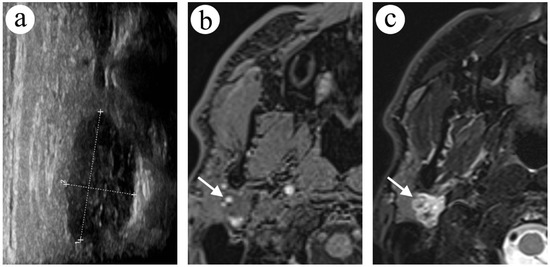

2.3. Case 3